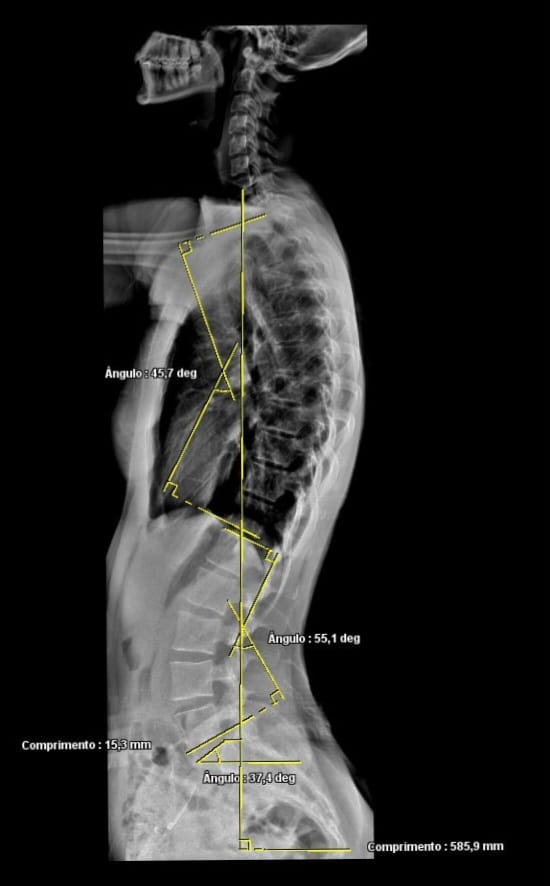

HSJ conta com atendimento de Raio-X completo de coluna para tratamento de escoliose

O HSJ agora conta com atendimento completo de Raio-X de coluna, auxiliando no diagnóstico e acompanhamento da escoliose com mais precisão e qualidade.

Com exames mais complexos e tecnologia avançada, o hospital amplia seus serviços para oferecer mais segurança, agilidade e cuidado para pacientes de Maravilha e toda a região.